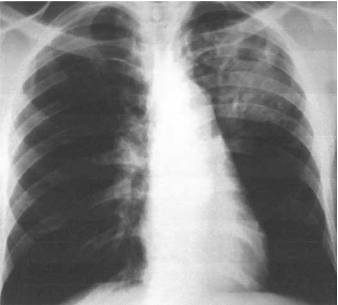

Homem de 59 anos de idade apresenta dispneia há cerca de 1 ano, inicialmente, aos grandes esforços, evoluindo para moderados e pequenos esforços. Exame físico: PA: 112 x 88 mmHg, FC: 112 bpm e FR: 16 ipm; ausculta pulmonar com crepitações em 1/3 de ambos os pulmões. radiografia realizada é mostrada a seguir.

Ao exame físico, a alteração que, mais provavelmente, deve ser encontrada é